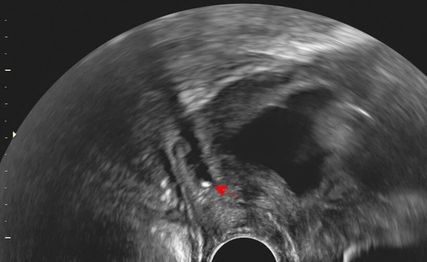

Abb. 2: Transvaginaler Ultraschall bei 17+4 SSW: prolabierende Fruchtblase mit Sludge

Notfallmässige Zuweisung einer 40-Jährigen (III Gravida I Para) bei 17+4 SSW aufgrund übermenstruationsstarker Blutung und prolabierender Fruchtblase (Abb.2). Die Schwangerschaft war durch eine intrauterine Insemination entstanden und bereits durch eine Imminensblutung in der Frühschwangerschaft kompliziert worden. Die Durchführung einer Pränataldiagnostik wurde von der Patientin nicht gewünscht. Die weitere Anamnese zeigte eine Vaginalgeburt am Termin fünf Jahre zuvor sowie einen Frühabort mit anschliessender Curettage zwei Jahre zuvor.